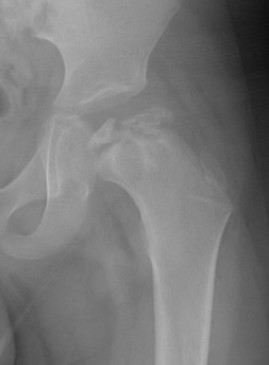

Femoral Varus Osteotomy (FVO)

Indications

Herring grade B or B/C

> 8 years at age on onset

Full containment of cartilaginous head

No hinge abduction